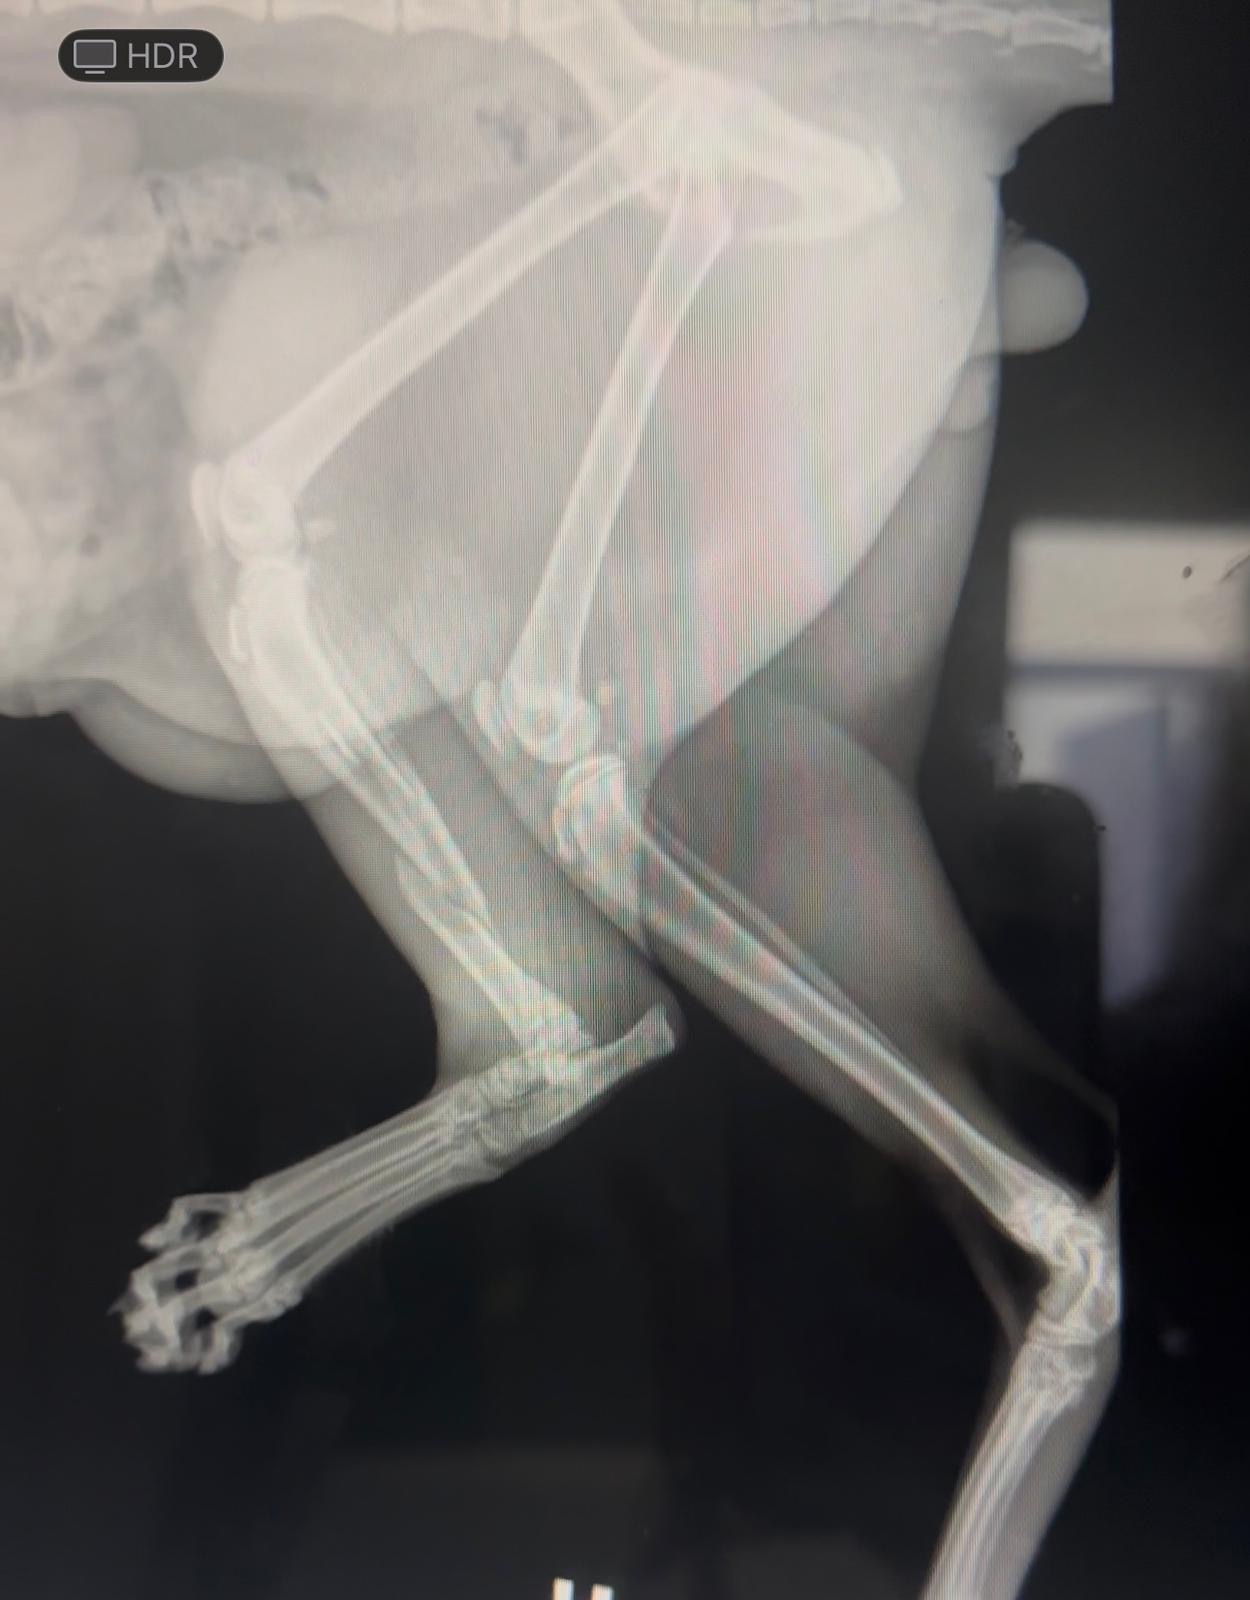

On June 1st, Lalo got in an unexpected accident, and we aren’t sure if he got hit by a car or got his leg stuck on something, but it was hard for him to walk, and he was in pain. I took him to the vet on June 2nd, where they gave him an exam and x-rays totaling $500. The doctor said my Lalo was overall healthy but had a tibial fracture on his left leg that needed surgery costing between $2,000 to $3,000.